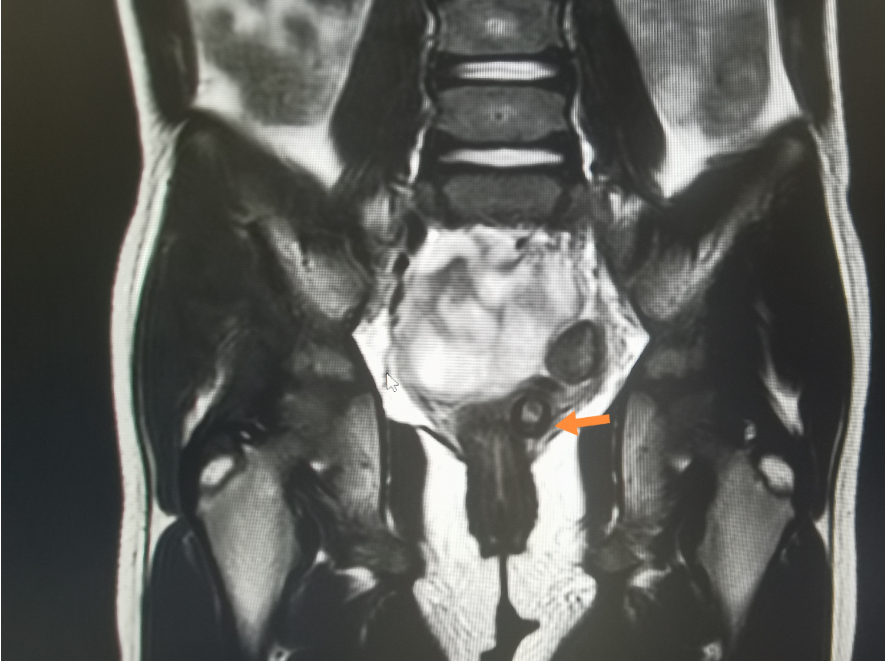

在给患儿完善了核酸检测及磁共振MRI检查后,医生发现报告结果提示阴道上段有两枚类圆形异物影。

在进一步肛查后,检查结果也显示可扪及阴道上段有两枚圆形的异物。

引发腹痛的原因有很多,比如囊肿等,鉴于孩子腹痛已经挺长时间了,医生建议家长先带孩子做影像学检查,检查结果提示有尖锐的物品在阴道穹隆-宫颈区里,正是这个“尖东西”引起的腹痛,医生当即意识到有异物,给孩子做了手术。